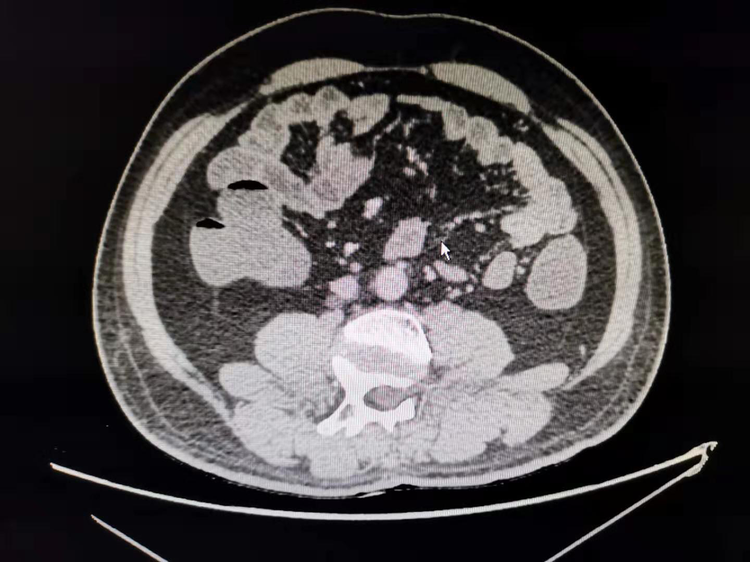

一例31岁男性患者,因“右侧腰背区疼痛1天”,行CT考虑为腔静脉后异位输尿管致肾积水,完善术前准备后为其行了"经腹腹腔镜下腔静脉后输尿管成形术",手术顺利,患者已出院。

一例为47岁男性患者,因“体检发现左肾积水”入院,行CT考虑左肾异位动脉后输尿管致肾积水,完善术前准备后为其行了"腹腔镜下异位肾动脉后输尿管成形术",手术顺利,已出院。